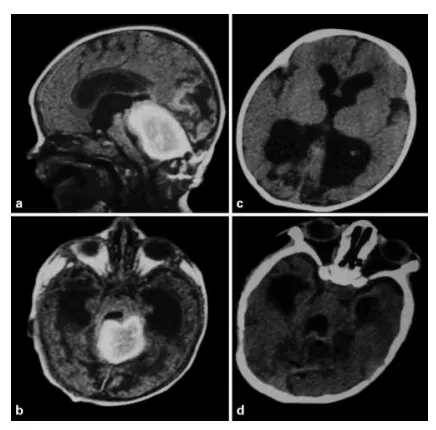

图2.a, b. 一名25天龄婴儿的矢状位及轴位磁共振T1加权像。该患儿因突发呕吐、呼吸困难及进行性意识障碍前来就诊。影像学显示一巨大血肿,累及整个小脑蚓部,伴有脑干移位及继发性急性脑积水。手术过程中未发现异常的动脉或静脉血管,提示诊断为破裂的海绵状血管瘤。c, d. 术后CT扫描显示血肿已被完全清除,相关的脑积水情况亦得到改善。3年后的远期随访结局令人满意,仅遗留轻微的共济失调症状。